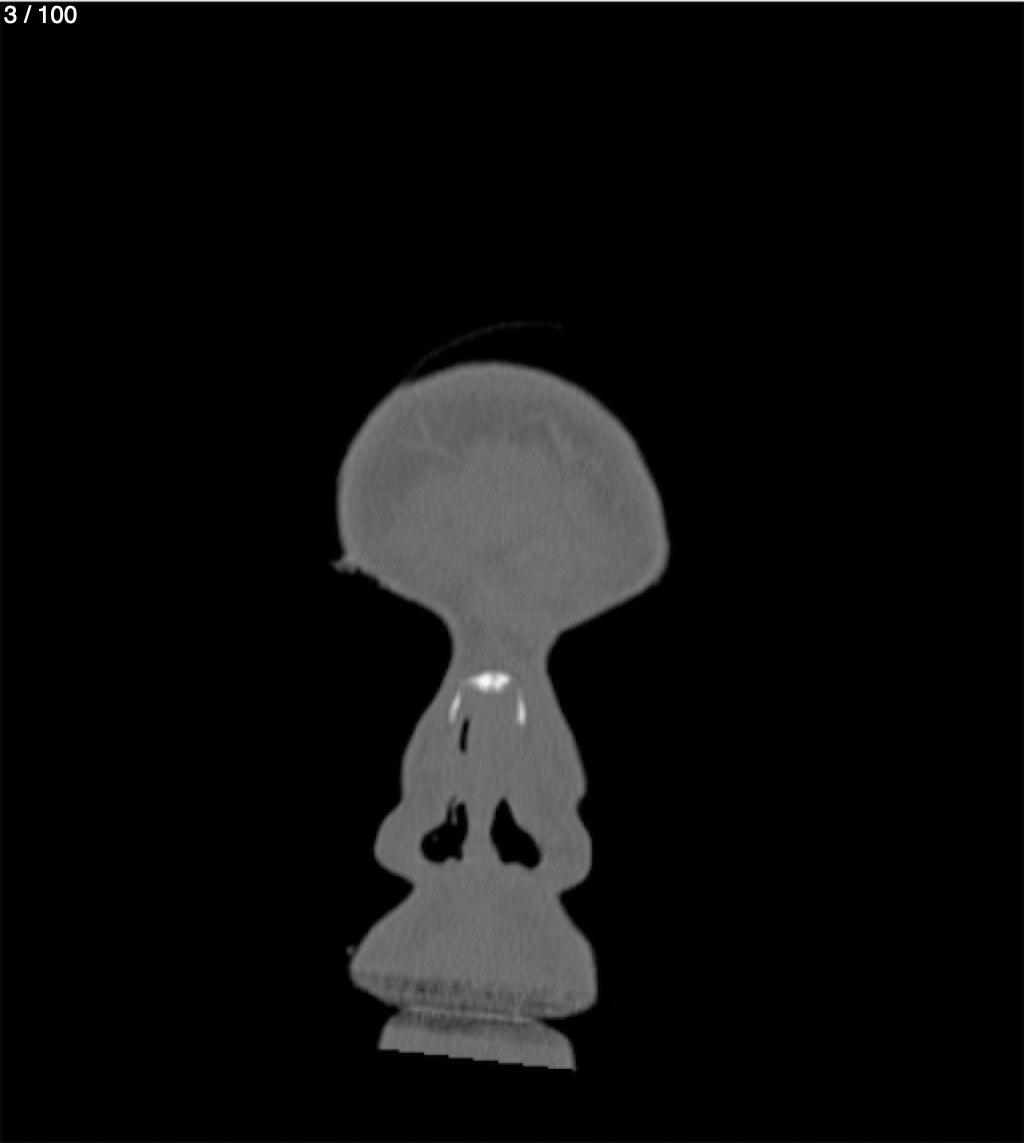

Reybet Garcia Fuentes 30A - T.C Craneo